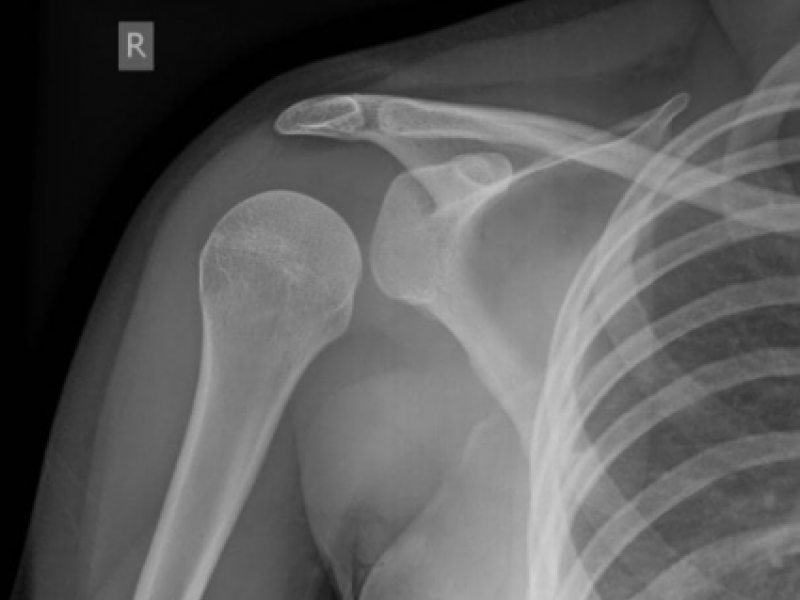

What's the Diagnosis? By Dr. Patrice Baptista

August 05 2020

A 4 yo M presents to Urgent Care with R shoulder pain after